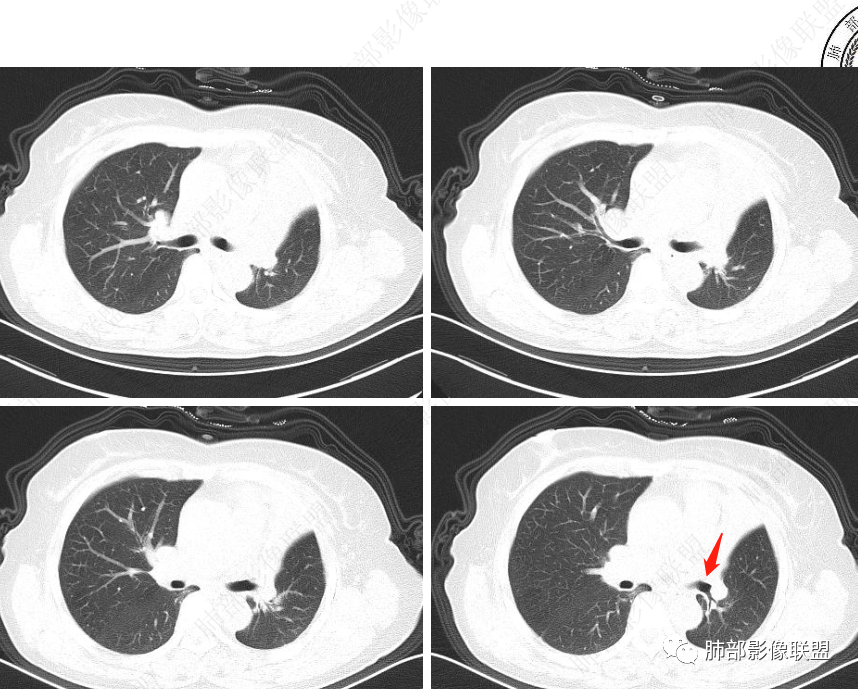

2、影像表现:正常肺背景,左肺上叶支气管腔内占位,上叶支气管截断,远端肺组织不张,强化差异衬托出肺门区结节影或块状影。增强扫描腔内占位轻中度不均匀强化,可见坏死,远端粘液栓,局部肺动脉受压、侵犯,纵膈淋巴结无明显肿大,无胸腔积液。

女,59,咳嗽4月。胸部CT:左上叶体积缩小,左肺上叶不张,叶裂平直回缩,左上叶支气管腔内见低密度软组织影,向腔内突入,远端粘液栓。增强血管走行清楚,腔内肿物中度强化。考虑左上叶腔内肿瘤伴左上叶不张,粘表?鳞?鉴别TB肉芽肿。